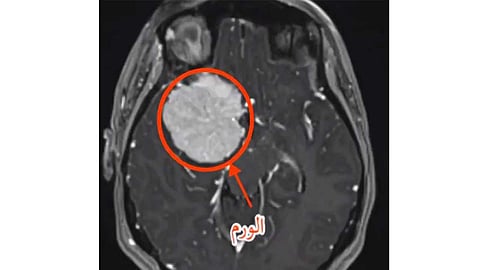

وعبر موقعه الرسمي، علق البروفيسور الجهني، على تلك العملية، قائلًا: شابة خليجية لديها صرع؛ بسبب ورم دماغي ضخم في قاع الجمجمة الأمامي ملتصق بشرايين الدماغ الرئيسية.. أحضرتها سفارة دولتها إلى باريس لأشهر بروفيسور في أورام قاع الجمجمة في أكبر مركز لجراحة الدماغ ليجري لها العملية.